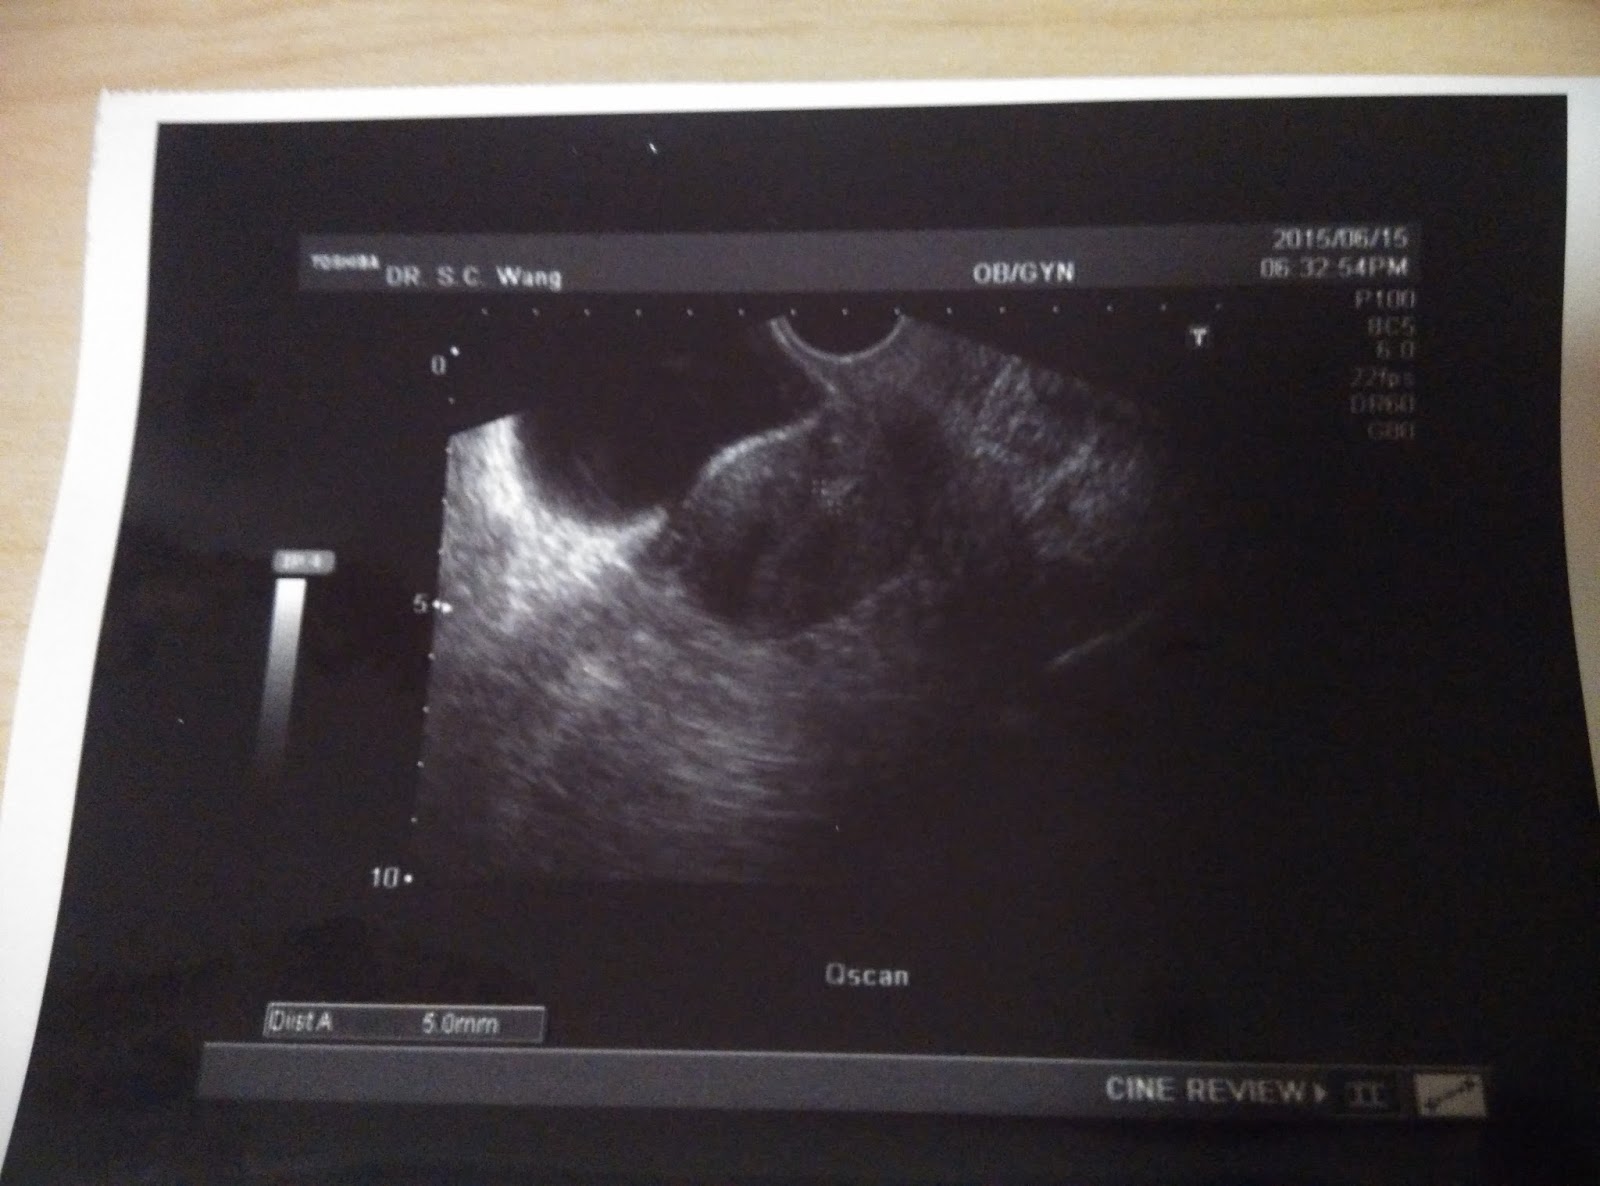

今天是我週期的第十二天,也是的要回黃醫生那邊覆診的日子。

這次去看醫生,主是想看看有沒有優勢卵泡。

之後醫生便馬上為我進行超聲波檢查。

我十分緊張,急不及待的問醫生有沒有比較大的卵泡。

醫生說有一粒成熟的,其餘的也是十分細小的。

我有多囊卵巢,所以這也是很正常的事。

其實只要有一個成熟的卵泡,我已心滿意足了。

我最大的那個卵泡在右方,直徑為1.67cm。

而左邊最大的卵泡,就只有1.23cm。

其實,如果只計卵泡,用了12天便有1.67,我已經很滿意了。

可惜內膜卻很薄,只有5mm,根本不適宜植入。

不過厚度已比上個月有進步了。

所以醫生開了E2給我服用,